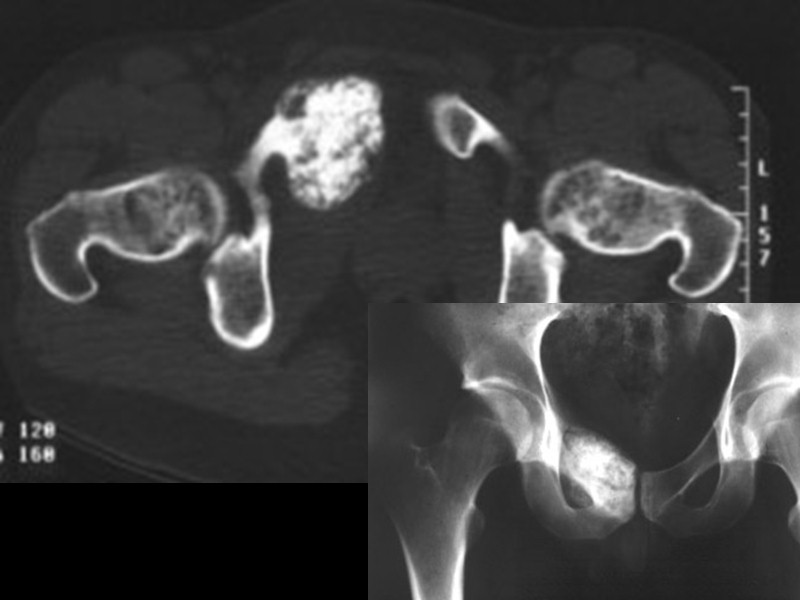

Аневризмальная костная киста Выявляется в возрасте от 5 до 30 лет Одиночная, состоит из сосудистых пространств, содержит венозную кровь. Преимущественная локализация – проксимальный метафиз длинных трубчатых костей (может переходить на эпифиз), реже – задние элементы позвонков,крылья подвздошных костей Располагается эксцентрично, дает сильное вздутие и истончение (может быть прерывание) кортикального слоя, имеет четкую склерозированную границу от окружающей кости Часто рецидивирует (50%) после выскабливания Может сочетаться с хондробластомой, фибромой, ОК, фиброзной дисплазией